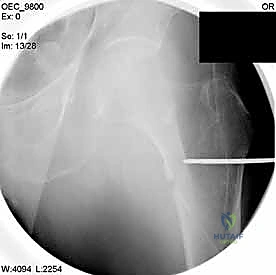

2. الرد المغلق تحت جهاز الأشعة (Closed Reduction)

قبل إجراء أي شق جراحي، يقوم الدكتور هطيف بسحب الساق وتدويرها بمهارة فائقة لإعادة العظام المكسورة إلى مكانها الطبيعي (المحاذاة التشريحية). يتم التأكد من ذلك باستخدام جهاز الأشعة السينية المتحرك داخل غرفة العمليات (C-Arm Fluoroscopy). هذه الخطوة حاسمة، فالرد الجيد يعني التئاماً ممتازاً.

مجموعة من الصور الإضافية التي توضح مراحل دقيقة من العمل الجراحي المعقد الذي يجريه الأستاذ الدكتور محمد هطيف لضمان أعلى درجات الدقة الميكانيكية الحيوية: